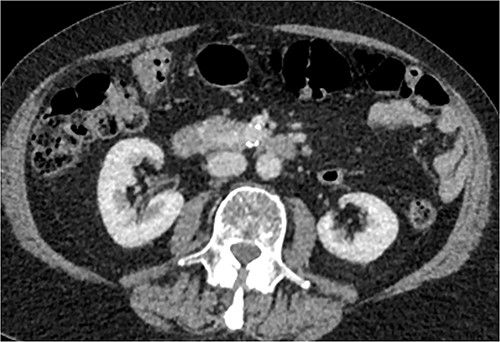

CT of abdomen and pelvis was performed, which revealed a 13 mm indeterminate lesion arising between the pancreatic uncinate process and the duodenum with coarse peripheral calcification, suspicious of primary pancreatic neoplasm or primary small bowel cancer (Figs 2–4).

Initial CT: axial view, demonstrating what was initially thought to represent indeterminate pancreatic/duodenal lesion.